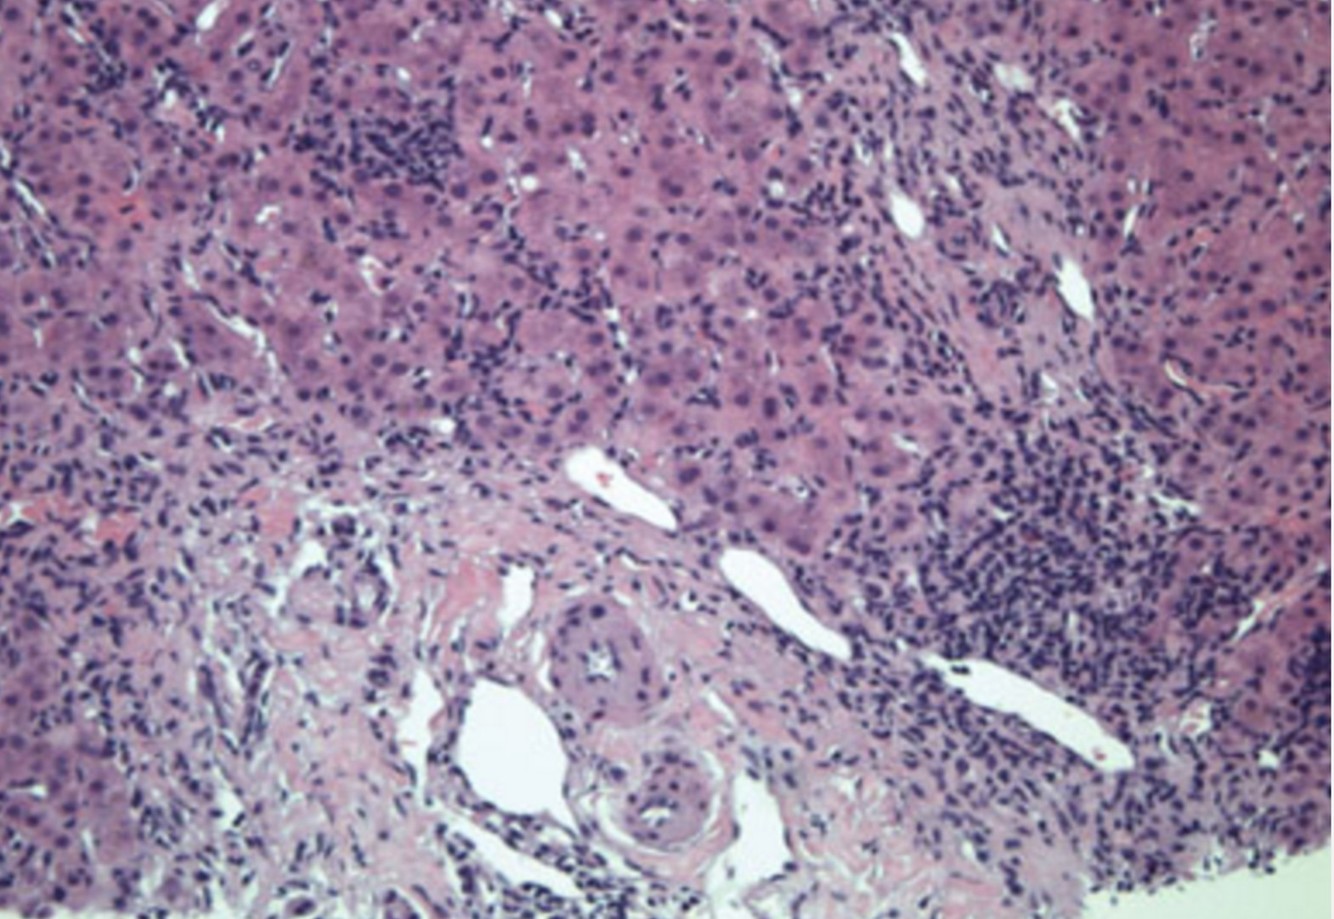

Kaposi sarcoma involving stomach

Four forms of Kaposi sarcoma (KS) are described:

(1) classic form, an indolent, primarily cutaneous disease typically affecting older men of Mediterranean ancestry

(2) endemic form, primarily affecting HIV-negative children in Africa

(3) iatrogenic form, affecting organ transplantation patients on immunosuppressive therapy

(4) HIV-associated cases.